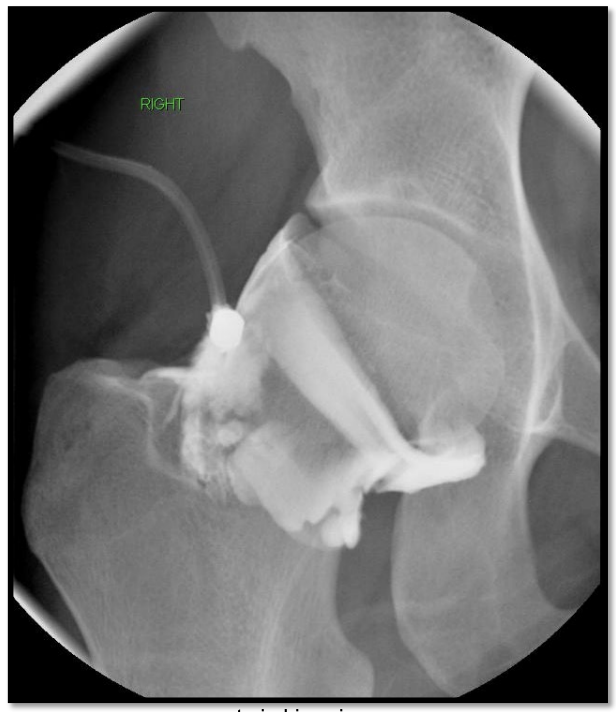

What is an Arthogram Pre MRI

A

• Some pathologies are not demonstrated with MRI

• A Labral tear in the shoulder is an example

• To see labral tears, contrast must be used

• MRI contrast is gadolinium (not seen with fluoro)

• Iodinated contrast and gadolinium mixed

• Fluoro can then be used to ensure that

gadolinium has been injected into the joint

can see tear in joint capsule @ 12 but not a full slap lesion